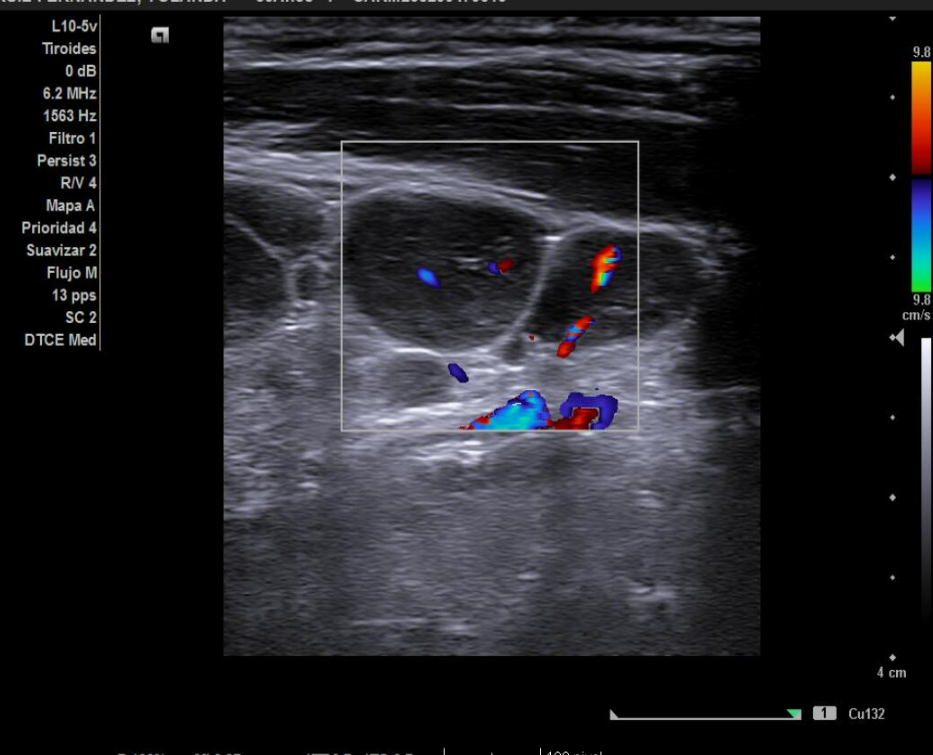

Se realiza ecografía en la consulta de AP (sonda lineal L10-5V). La gran mayoría son adenopatías subcentimétricas, con hilio central hiperecogénico y vascularización central. Se amplía estudio con analítica y una interconsulta a Hematología.

En la analítica se objetiva ligera leucopenia y neutropenia. Serología positiva para IgG frente a virus Epstein–Barr. Resto de parámetros normales, incluidas VSG y PCR. Tras 3 semanas se realiza nuevo control ecográfico, observándose cambios respecto al estudio previo: agrandamiento de adenopatías mayores de 10 mm, hipoecogénicas, en conglomerado, con pérdida del hilio y aparición de una adenopatía supraclavicular derecha de 14 mm con vascularización periférica. Estos hallazgos resultan sugestivos de proceso linfoproliferativo, por lo que se tramita derivación preferente a Hematología con solicitud de PAAF, que se realiza en 48 horas. Tras su valoración, la paciente ingresa para completar estudio.

La ecografía en Atención Primaria permite identificar signos ecográficos de alarma en adenopatías (cociente longitud/anchura > 1,3, redondeamiento, ausencia de hilio, alteración cortical, vascularización periférica o aberrante). Su uso agiliza el diagnóstico, optimiza recursos y mejora la capacidad resolutiva. En este caso fue determinante para sospechar patología maligna y priorizar el estudio hematológico, facilitando un abordaje precoz y multidisciplinar.